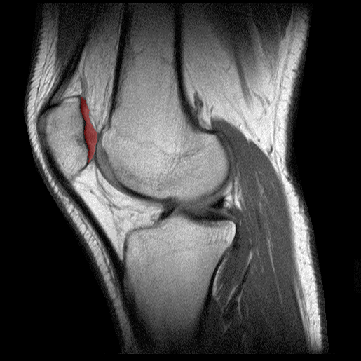

CARTILAGO ROTULIANODescripción: La parte posterior de la rótula está recubierta por la capa más gruesa de cartílago hialino que existe en el cuerpo. Origen: Las tres cuartas partes superiores de la rótula están cubiertas por cartílago hialino de 5 a 6 mm de grueso. La cuarta parte inferior de la rótula es superficie no-articular y no está recubierta por cartílago. Función: Amortiguación de los choques producidos durante las flexiones. El reblandecimiento del cartílago rotuliano (condromalacia rotuliana) es una cause frecuente del dolor de rodilla.